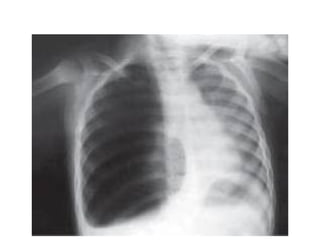

DERRAME SUBPULMONAR

• Con menor frecuencia la localizacion del derrame semeja

una elevacion del hemidiafragma y su presencia puede ser

demostrada con una rx en decubito lateral con rayo

horizontal o con ecO

DERRAME MASIVO

• Desplazara al mediastino hacia el lado contrario, si esto no

ocurre se debe sospechar en malignidad debido a

obstruccion bronquial con atelectasia pulmonar, fijacion

del mediastino como ocurre con la infiltracion tumoral de

los ganglios linfaticos y atrapamiento del pulmon en el

mesotelioma maligno